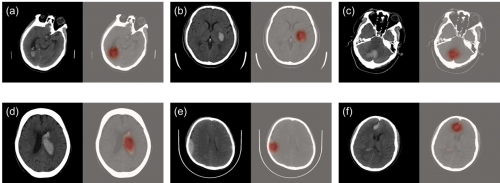

科亚医疗的“CuraRad-ICH” 是一款专注于对脑卒中进行快速脑部出血预警的AI影像分析处理软件,可以通过深度学习技术准确、快速地筛查急性脑出血病例,并直接无缝接入医院PACS系统, 自动升高脑出血病例的优先级,提示影像科医生优先完成病患的诊断评估,从而有效缩短脑卒中病患的诊断治疗时间,挽救生命。

在来自全美48个州296家影像中心的临床测试中,CuraRad- ICH分析处理软件达到了91%的敏感性和93%的特异性,同时平均每次预警仅耗时43秒,大幅度缩短出血性脑卒中病患的诊疗时间,受到临床专家的一致认可。